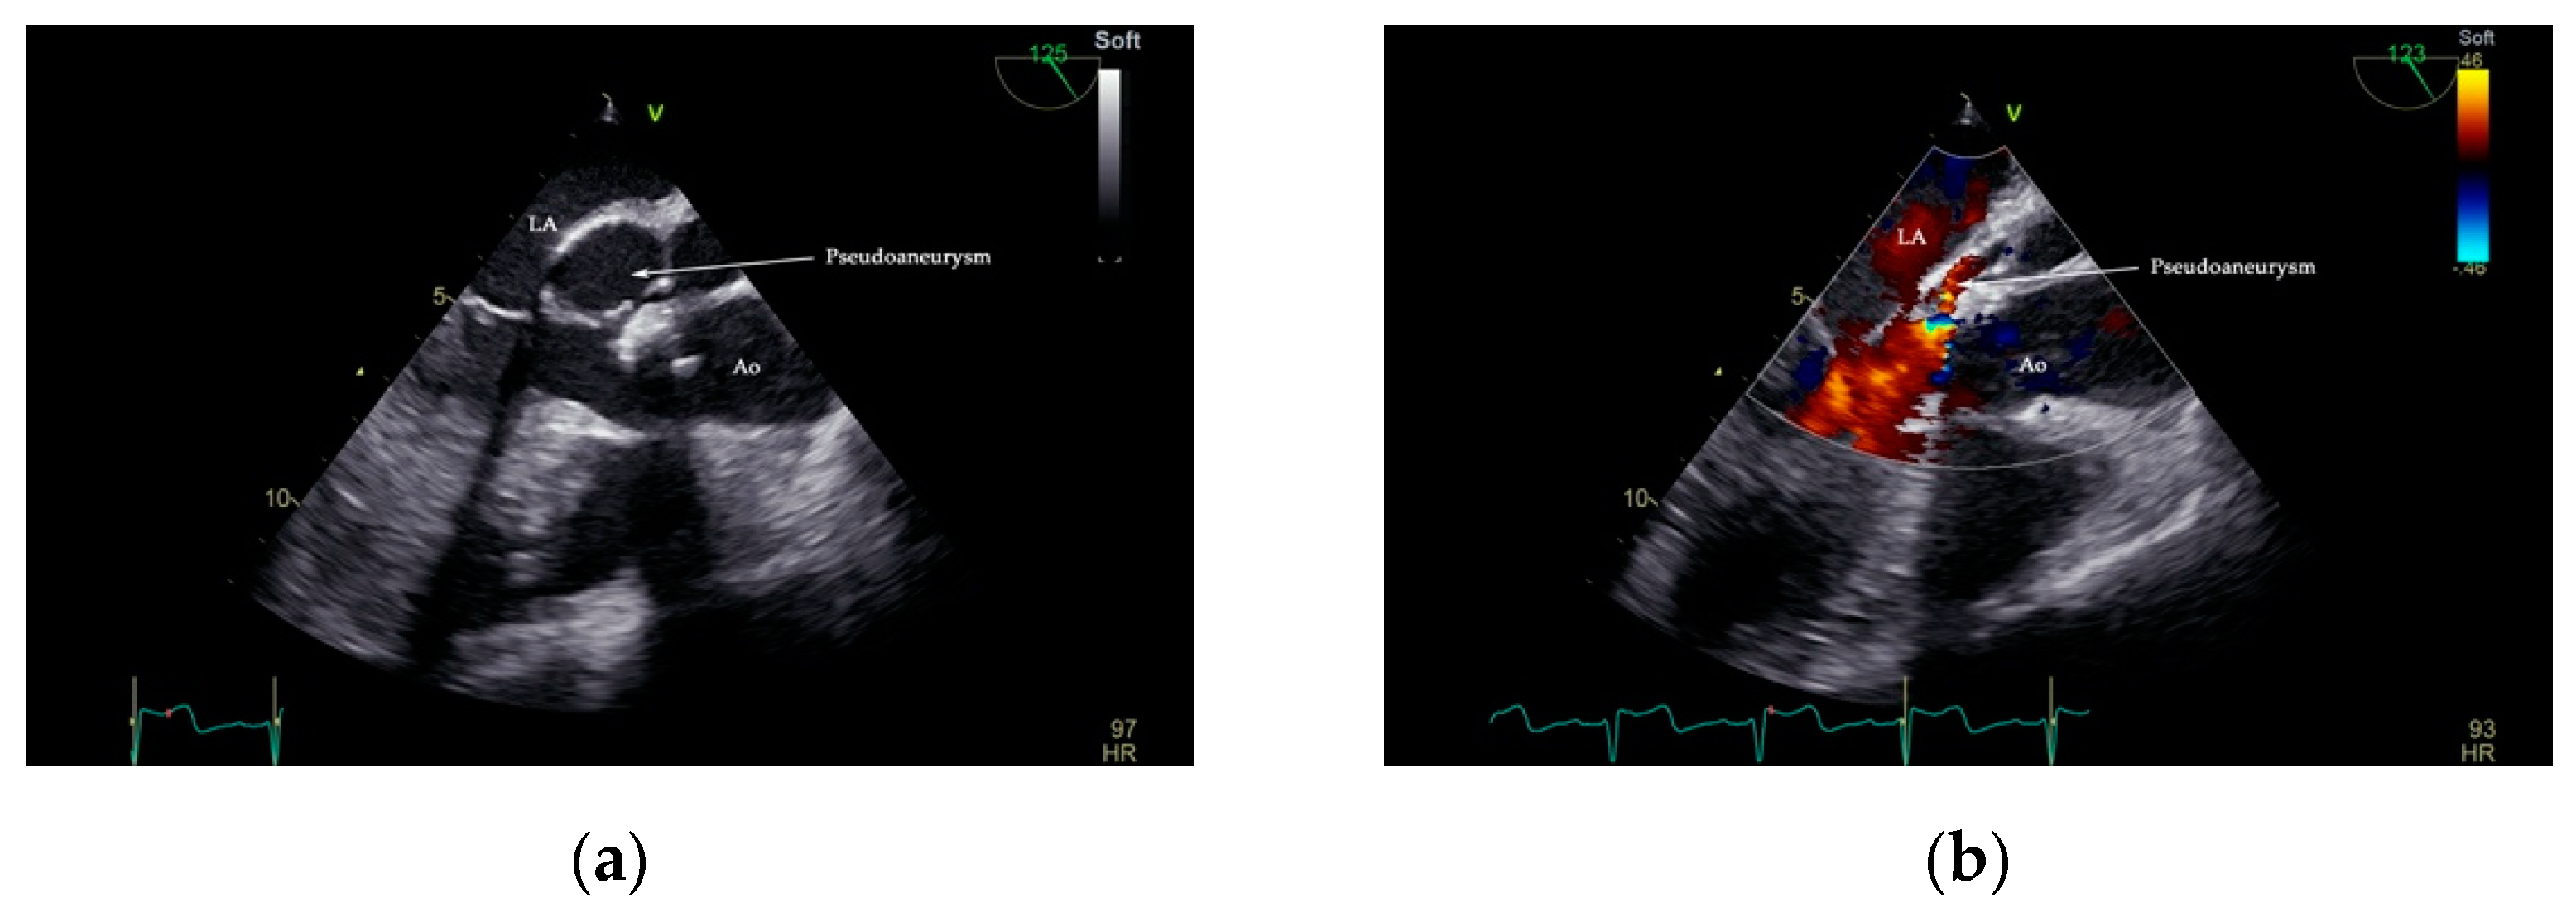

2. Case Presentation